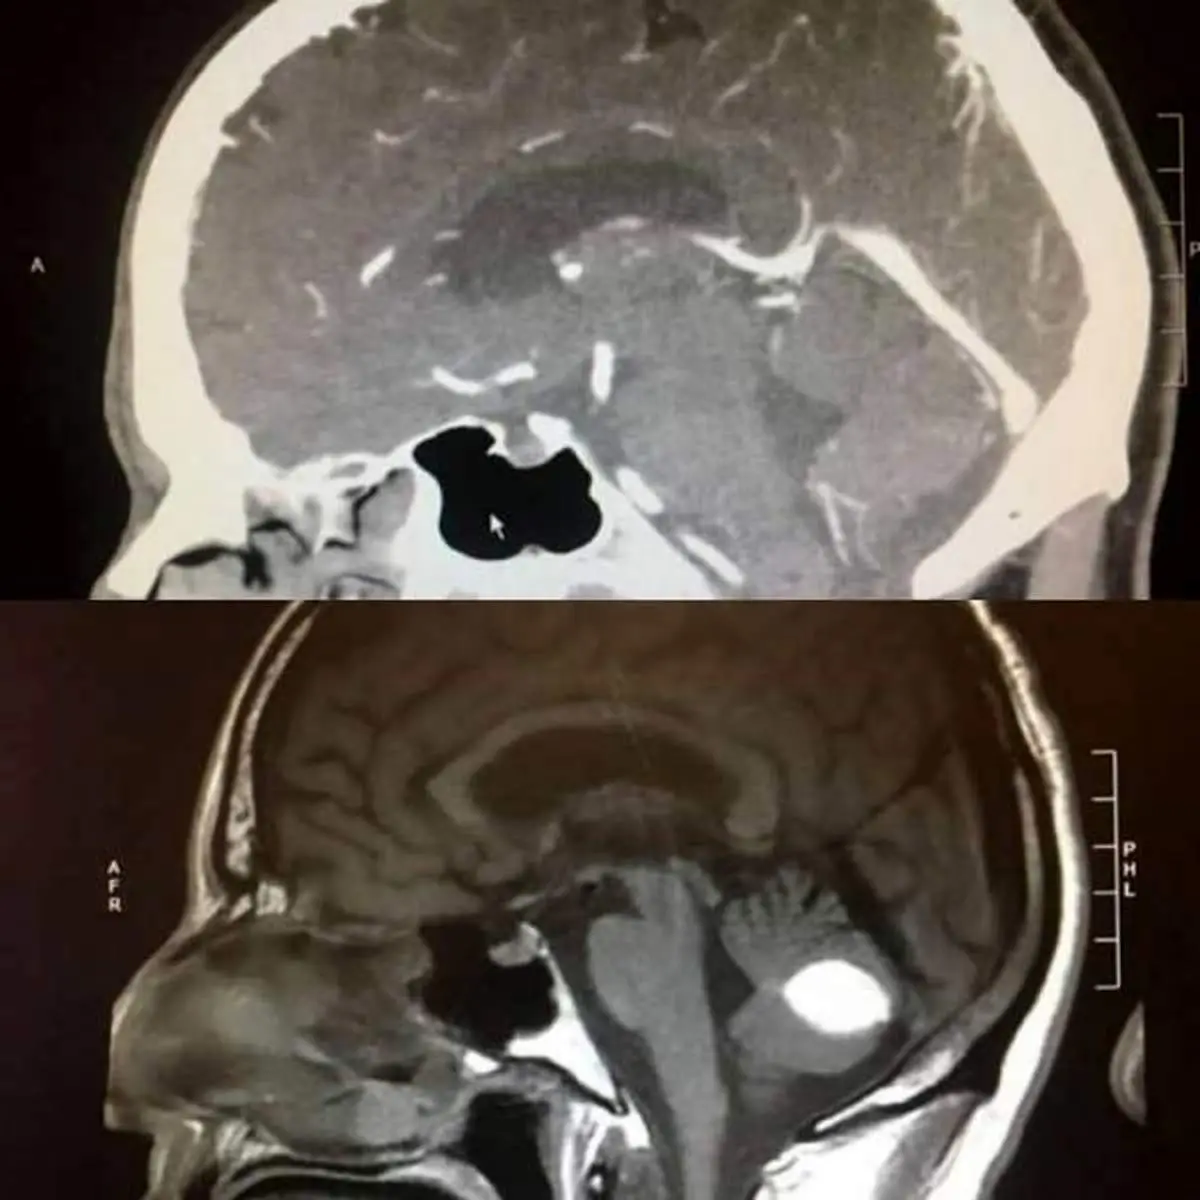

آقای " پائول وود " یکی از ساکنان کالیفرنیا می باشد که اخیرا به شدت احساس سرگیجه و سر دردهای فراوان داشت و به همین دلیل تصمیم گرفت تا علت آنرا جویا شود. از این رو، وی تصمیم گرفت تا سی تی اسکن از ناحیه جمجمه خود انجام دهد که یکی از پزشکان سانفرانسیسکو، علت را خونریزی مغزی دانست و این در حالی بود که یک رادیولوژیست در نتیجه اعلام کرد که وی مبتلا به تومور مغزی است!با این وجود هر دو پاسخ منتهی به جراحی سنگین مغزی مرتبط بودند و وی برای رهایی از این آسیب تصمیم گرفت تا جراحی شود. در همین حین، یک روز قبل از جراحی، مجددا تحت سی تی اسکن قرار گرفت و این سی تی اسک باعث گیج و دست پاچه شدن پزشکان شد چرا که در سی تی اسکن آخر، تومور مغزی به صورت معجزه آسایی ناپدید و غیب شده بود!

گفته می شود پزشکان هنوز در این مورد هیچ پاسخی به عنوان توضیح ندارند که چه اتفاقی در وی رخ داده است و اما آقای وود بنابر اعتقادات خود به خدا، معتقد است که این تنها معجزه ای از جانب خدا بوده است.